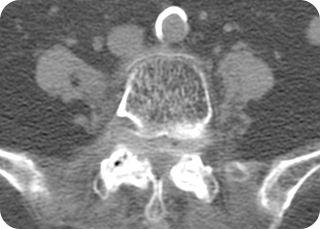

3

CT검사 (척추뼈, 인대석회화, 척추관절)

몸 안의 구조나 조직을 횡단면으로 보여주는 검사 방법입니다. 뼈의 모양과 연결 상태를 보여주는 엑스레이와 달리 허리디스크와 척추 관절의 변성, 비후된 인대도 잘 보이므로 척추관협착증 등을 알아볼 수 있습니다.